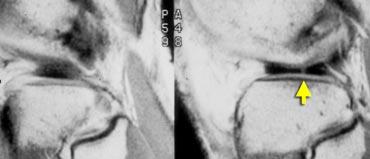

TRÁI: chân bám sụn chêm trong bình thường nằm ngay phía trước dây chằng chéo sau. PHẢI: mất chân bám sừng sau do rách chân bám sụn chêm.

Chân bám sừng sau nằm ngay phía trước dây chằng chéo sau.

Nếu không thấy chân bám này trên các lát cắt sagittal, cần nghĩ đến rách chân bám sụn chêm (hình minh họa).